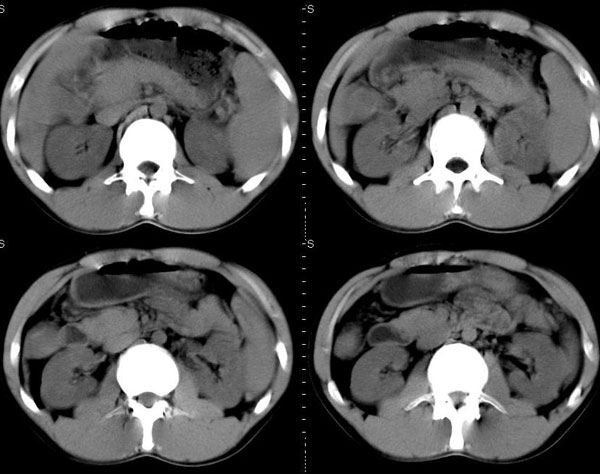

以下是引用晓杰在2006-8-26 21:18:00的发言:[br]肝右叶前段片状低密度灶,边缘模糊。肝内胆管扩张。考虑肝ca? 肝脓肿?[br][br][br]胰头增大,结构模糊,考虑:占位病变。建议增强